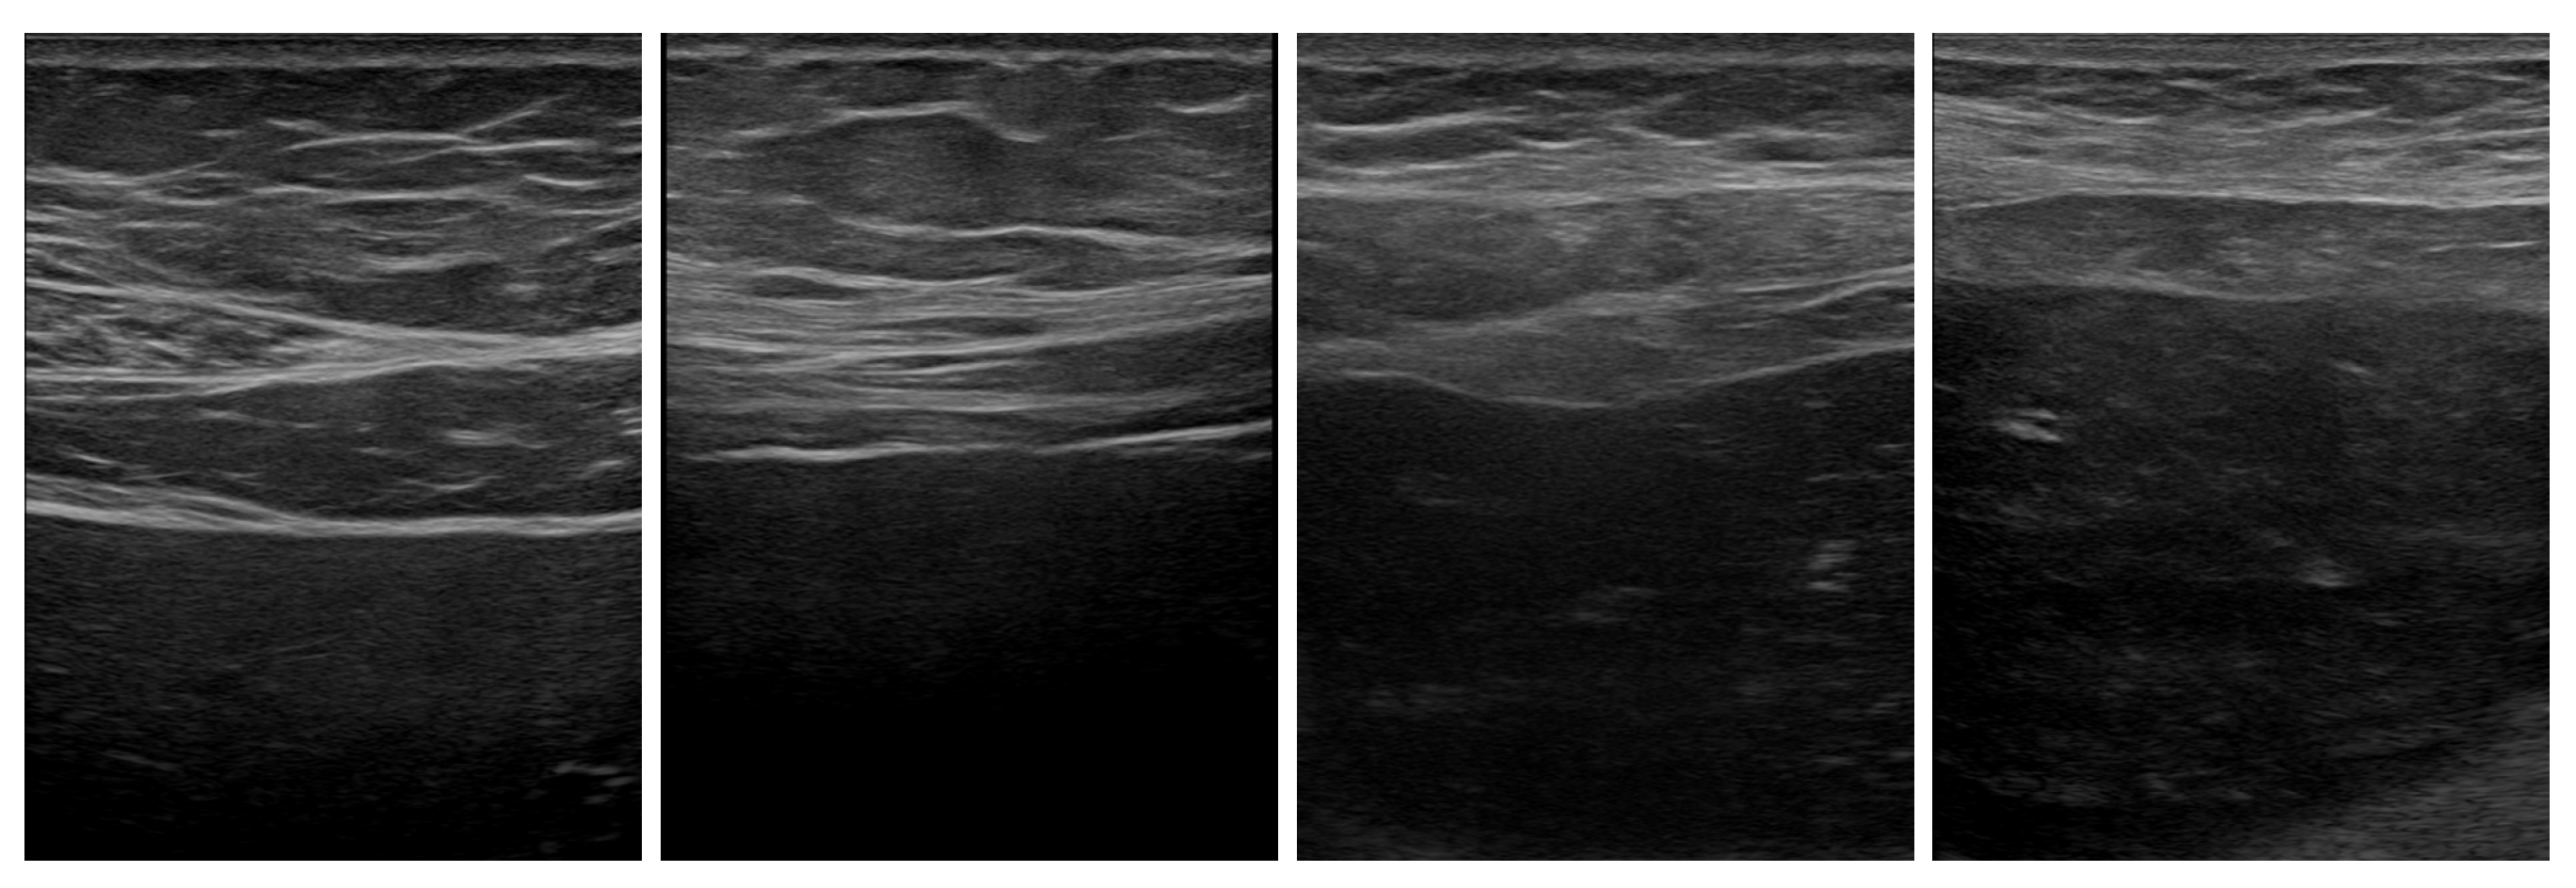

This retrospective study, conducted at Ospedale Policlinico San Martino IRCCS in Genoa, involved 215 CLD patients (male and female) with an average age of 57.84 ± 13.39 years (range 20–92). Patients were diagnosed with conditions such as non-alcoholic fatty liver disease (NAFLD), hepatitis C (HCV), hepatitis B (HBV), autoimmune hepatitis (AIH), and primary biliary cholangitis (PBC). The dataset Figure 1 included 392 liver ultrasound images acquired using the M y L a b T M X 9 Esaote machine.

Figure 1. US original images from Esaote M y L a b T M X 9 ultrasound scanner. From left to right, the stages correspond to fibrosis progression from F0–F1 to F4.